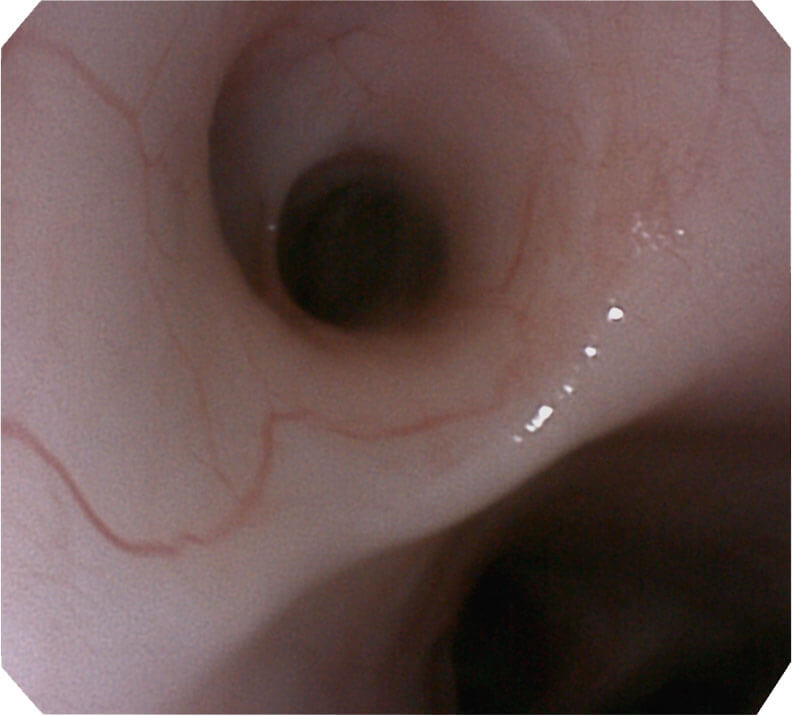

高分辨率画质

帮助医生更加清晰地观察气管表面病灶

大视野角

120°视场角,满足更大视野范围的观察。配合 VIST 染色,助力呼吸系统疾病的诊断。